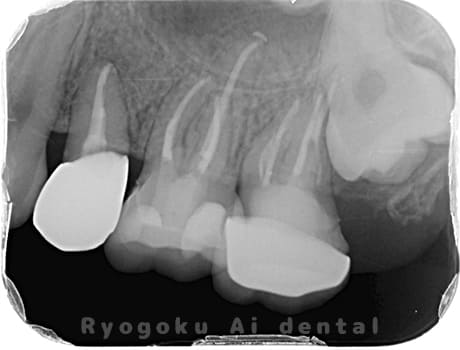

Case04

-

- 原因

- 慢性根尖性歯周炎

- 治療期間

- 3ヶ月

- 治療内容

- マイクロエンド

- 治療費用

- 121,000円

噛むと痛みが出る、とのことで来院した患者様です。他院での根管治療を終えてましたが、根尖病変を認めるため、マイクロエンドを行いました。